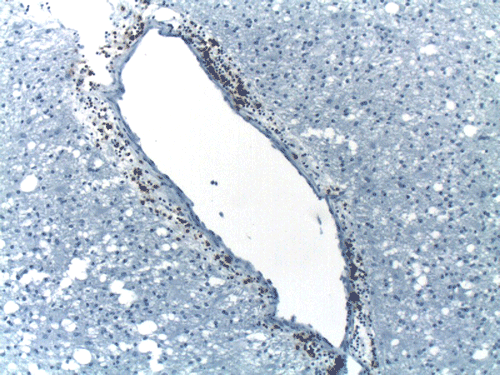

A left frontal lobe biopsy was performed and yield the following representative photomicrographs.

On CT scan, there is multiple hypodense white matter lesions that appear to spare a thin layer of subventricular white matter (Panel A). The T2-weighted images on MRI provides a more accurate estimation. The white matter in the occipital lobes is most affected (Panel A). There is extensive vacuolar changes in the white matter (Panel B and C) and there is a questionable increase in cellularity. In some of the thin walled blood vessels, there is a thin layer of perivascular lymphocytic infiltration which is free of atypia (Panel D, E, and F). The lymphocytes do not appear to extends into the parenchyma. On higher magnification, some large reactive astrocytes can be seen (Panel G). In a minority of areas, some concentric rings can be seen on hematoxylin-eosin stained sections (Panel H). These rings appear to be alternating rings of myelinated and demyelinated white matter and the vacuolar changes appear to be limited mainly to the concentric lesions. The adjacent myelinated areas are spared (Panel I). In some areas, the level of myelin loss appears to be proportional to the level of vacuolar changes (Panel J and K). On immunohistochemistry for glial fibrillary acidic protein (GFAP), the degree of gliosis is also more impressive in areas with more prominent vacuolar changes (Panel L and M). The vacuolar areas also appear to have a reduced density of axons (Panel N). Axonal spheroids are also present in these areas (Panel O). Although a prominent infiltration of foamy histiocytes is not noted on hematoxylin-eosin stains, immunohistochemistry for CD68 illustrated positive cells in a minority of demyelinated areas (Panel P). These cells lacks the foamy nature of macrophages and their morphology would suggest microglial cells. The reactive astrocytes are not immunoreactive for CD68 (Panel Q). Immunohistochemistry for T-cells (CD3) and B-cells (CD20) demonstrates only a thin rim of perivascular infiltration without significant extension into the surrounding parenchyma (Panel R, S, and T).